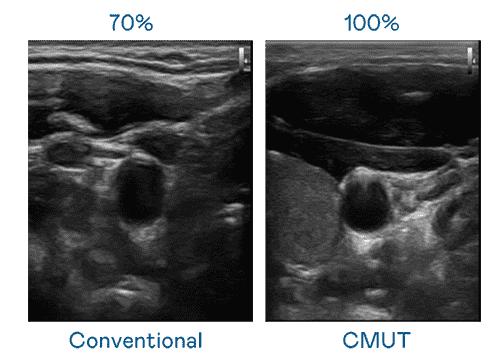

CMUT 技术是一种用电容式微机电元件来产生超音波讯号的技术。。与传统 PZT 压电式技术相比,,,CMUT 频宽增加 30%,,更宽频的超音波讯号让影像解析度大幅提升,,,是实现高影像品质医疗超音波扫描、、促进精准医疗发展的关键技术。。。

大频宽带来超清晰影像

超音波影像的解析度高低,,,首先取决于探头能发出的讯号频宽。。。开云电子 CMUT 可提供高清晰的超音波讯号,,,提供高频宽、、高灵敏度、、影像纹理细节更高的超音波影像,,,,协助医护人员缩短影像判读时间及利用精准的医疗影像进行诊断。。。。